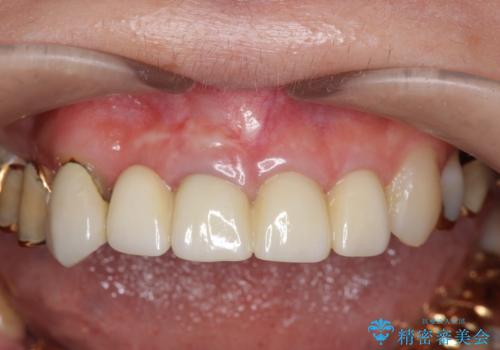

- 54万円(仮歯・感染根管治療・ファイバーコア・ジルコニアクラウン×4) (税別)費用は治療当時の料金となります

歯列全体を治療の対象とする治療計画が予算や期間により難しい場合、状況に応じて最善の治療結果が出せるよう治療のゴールを相談しながら決定することが可能です。